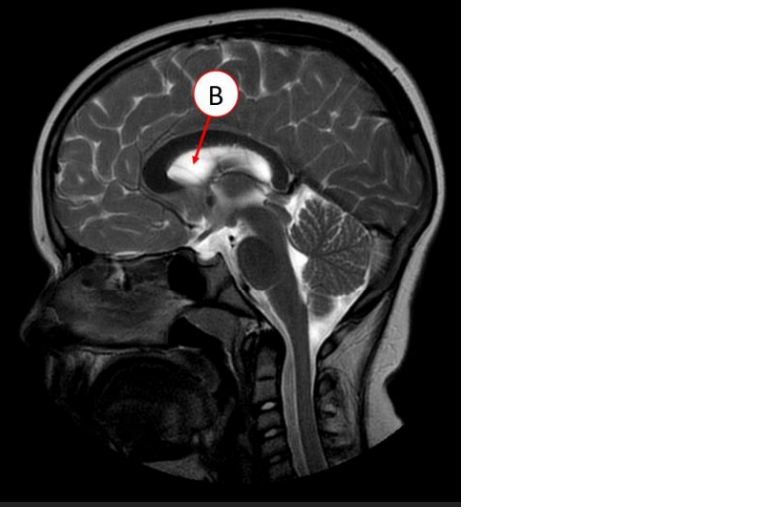

corpus callosum

ventriculus IV

Aquaeductus mesencephali

Thalamus Dex.

hypophysis

plexus choroideus ventriculi III

ventriculus III

komora III